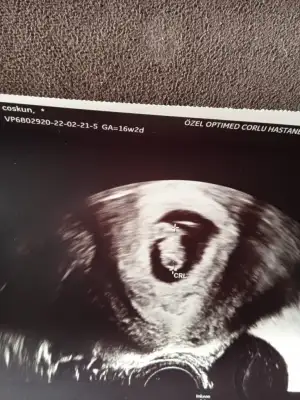

nasılda kapanmış içine doğru14+1 karından ultrason bizimki göstermedi de merak ediyorum :)

Kız de sen yine de kız olsun Allahımnasılda kapanmış içine doğrucanım bilemedim ama sanki paşa gibi